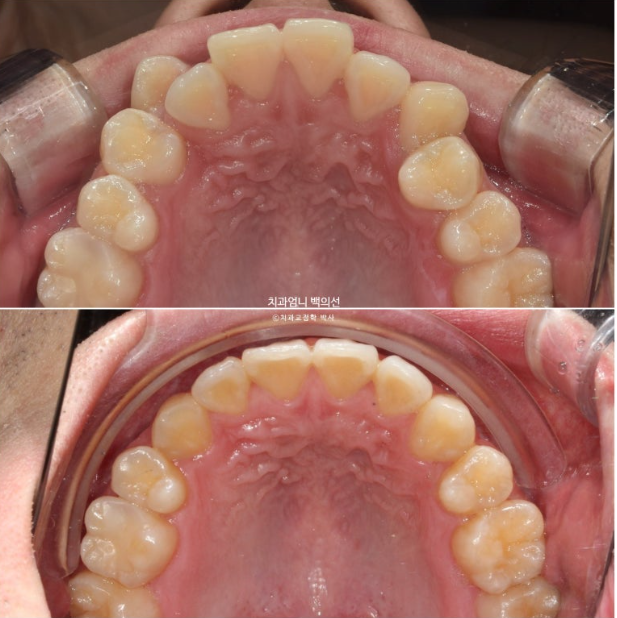

이제 전 후 비교 보겠습니다.

22.09~25.04

교정치료의 기본은 물샐틈 없는 이븐한 교합입니다.

교합이 좋지 않으면 교정치료를 마무리 짓지 않습니다.